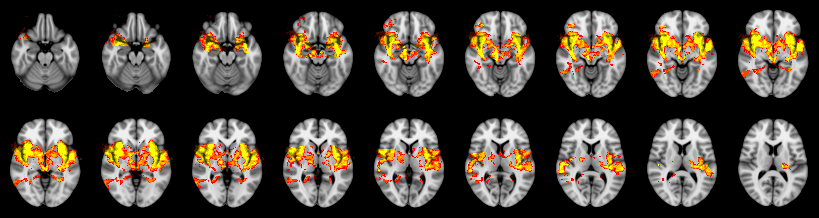

Pain study, TFCE, Uncorrected

Combined

Friston:

IUT/Conjunction/Nichols:

Hotelling T2: